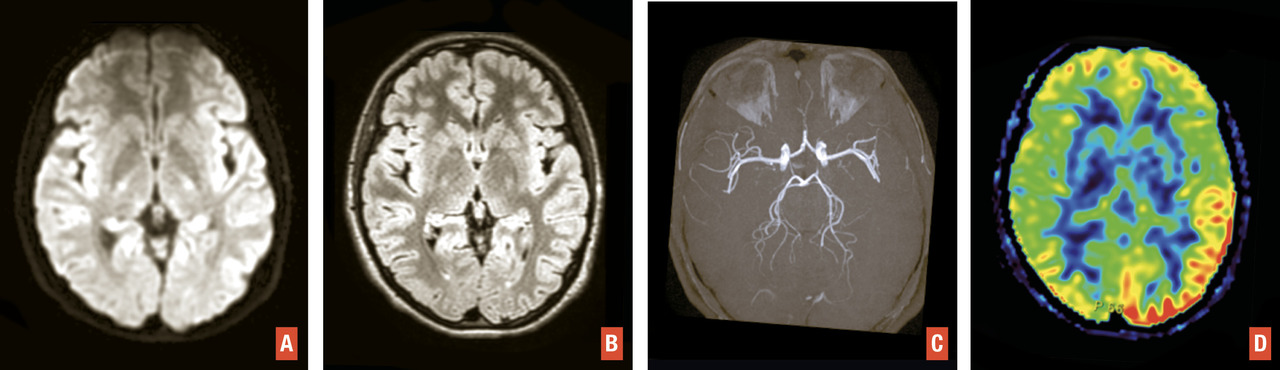

L’IRM est l’examen recommandé en France, si le plateau technique le permet sans retarder la prise en charge, et en dehors des contre-indications. Elle a une excellente sensibilité et spécificité pour détecter l’ischémie cérébrale aiguë. Un protocole standardisé est réalisable en moins de 10 minutes sans retarder la décision thérapeutique3 avec quatre séquences clés (– la séquence de diffusion pour détecter des lésions ischémiques récentes, en hypersignal avec baisse du coefficient apparent de diffusion, traduisant la restriction des mouvements des molécules d’eau secondaire à l’œdème cytotoxique. Bien que plus sensible que la tomodensitométrie, de rares faux négatifs peuvent s’observer en séquence diffusion en cas de lésion de petite taille, notamment de la fosse postérieure, d’examen très précoce ou de déficit transitoire ;

– la séquence de susceptibilité magnétique (T2* ou SWI) pour détecter un hématome,1 des séquelles hématiques ou une transformation hémorragique de lésions ischémiques, en particulier après traitement de recanalisation. Le thrombus artériel apparaît en hyposignal artériel linéaire ou curviligne en T2*, dont la sensibilité varie selon la composition du caillot, sa taille et le type de séquence utilisée ;

– la séquence FLAIR, qui permet d’apprécier l’étendue de la leucopathie vasculaire et les séquelles d’infarctus anciens, de dater l’infarctus (classiquement non visible avant 3 heures),1 de rechercher des hypersignaux vasculaires, en rapport avec des ralentissements vasculaires dans les artères collatérales en aval de l’occlusion ;

– l’angiographie par résonance magnétique (angio-IRM) 3D temps de vol du polygone de Willis (sans injection) afin de rechercher une occlusion ou une sténose des artères intracrâniennes. La séquence de perfusion T2* peut également être réalisée. Comme en tomodensitométrie, elle permet d’apprécier le risque d’extension de l’infarctus (« mismatch » perfusion-diffusion) et de décider d’un traitement de recanalisation dans des situations particulières (heure de début des symptômes inconnue, délai tardif)1 [

Ils représentent près de 20 % des suspicions cliniques d’AVC. L’IRM est plus performante que la tomodensitométrie pour distinguer un infarctus d’une pathologie non vasculaire. Les trois principaux diagnostics différentiels sont : déficits post-critiques, aura migraineuse, déficit « anorganiques » et, plus rarement, hypoglycémie, tumeurs cérébrales… En IRM, les anomalies ne sont pas systématisées à un territoire artériel et il n’existe pas d’occlusion artérielle.4 L’IRM permet d’orienter rapidement vers ces diagnostics différentiels et de proposer une prise en charge adaptée dès le stade aigu (fig. 4 ).